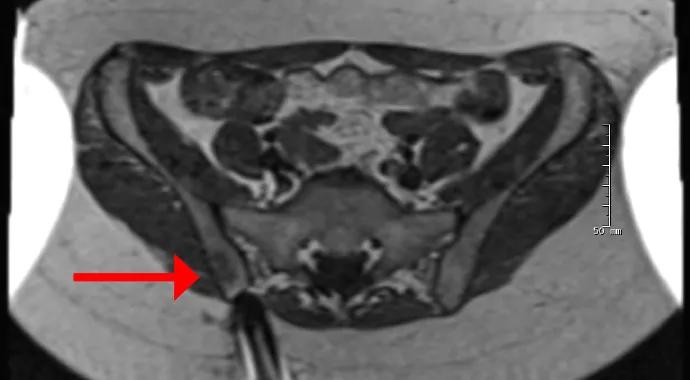

Immediately after receiving a nondiagnostic biopsy result, the patient came to Cleveland Clinic for a second opinion. We performed MRI-guided biopsy of the pelvic lesions (Figure 1), and histology showed extensive granulomatous inflammation consistent with sarcoidosis and no evidence of a neoplasm.

Figure 1. T2-weighted MRIs during and after the biopsy. On the left is an axial image showing the needle approaching the bone lesion (arrow). The middle image shows the needle tip within the lesion. The right image, which is from a post-biopsy coronal STIR sequence, shows the needle tracks (two bright round areas denoted by arrows) from the patient’s two biopsies, which are surrounded by abnormal signal consistent with a lesion.